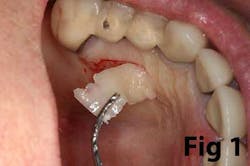

The free gingival graft (FGG) (Fig. 1) is an age-old periodontal procedure first described by Sullivan & Atkins in 1968. (9) It has long been the gold standard for increasing attached gingiva around the natural dentition. Connective tissue grafting (CTG) (Fig. 2) provides many of the same benefits along with root coverage, without the accompanying discomfort from the donor site, making the FGG less desirable. However, the FGG procedure has its advantages over CTG for both the natural dentition and, more recently, dental implants.